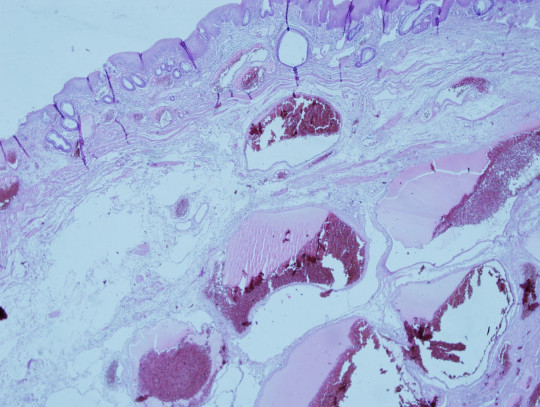

Obr. 46. Histologický preparát – hemoroidy.